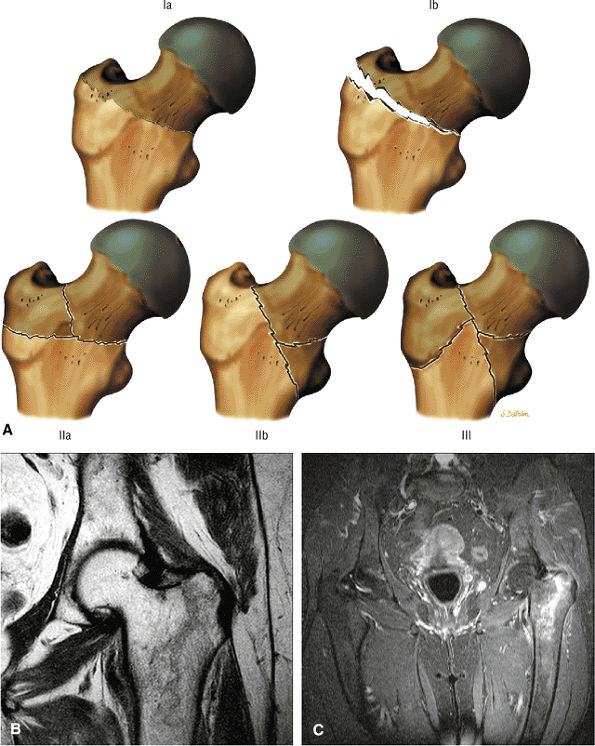

Stage III: The onset of stage III disease is marked by the loss of the spherical shape of the femoral head (Fig. 3.81). The AP radiograph may appear normal, but the lateral view often reveals a crescent sign, or radiolucency, under the subchondral bone. This represents a fracture between the subchondral bone and the underlying femoral head (Fig. 3.82). The crescent sign is the

earliest indication of mechanical failure from accumulated stress fractures of nonrepaired necrotic trabeculae.27 At this stage, there is also separation of the subchondral plate from the underlying necrotic cancellous bone. The necrotic area becomes radiodense (Fig. 3.83) as a result of mineral deposition in the marrow spaces. The joint space remains preserved or may actually increase in height. -

Stage III: Crescent sign lesion and depression of the femoral head articular surface